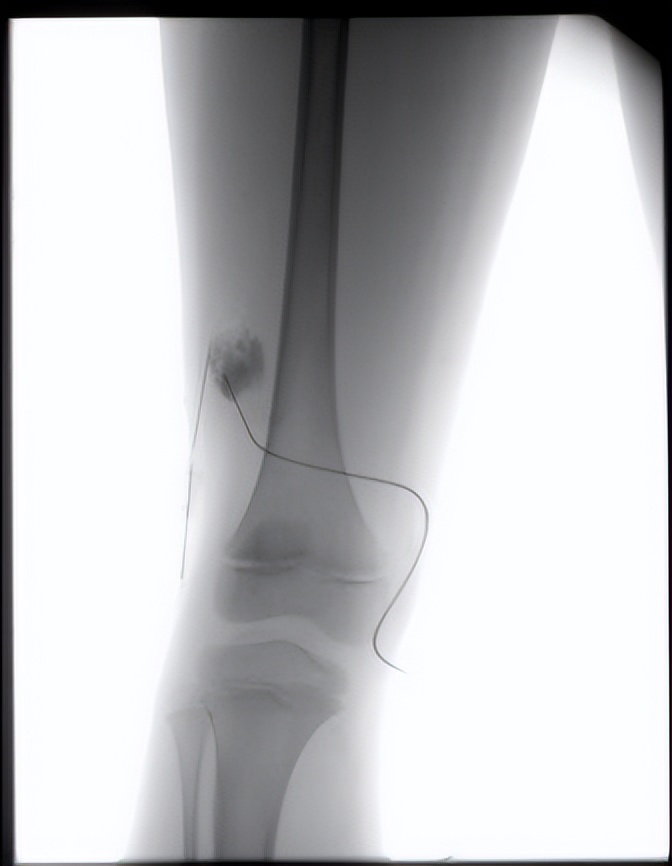

而且随着抽液,囊不见小!我团队人员立刻发觉这不是淋巴管瘤,随即,立刻为患儿做了造影,造影显示畸形静脉显影,引流静脉也显示出来,确定这是静脉畸形,然后按照静脉畸形的处理方式,经皮注射造影剂,确定是畸形的血管团后,局部注射硬化剂,注射硬化剂后局部皮肤略发白,使得血管内皮细胞破坏,从而达到治疗的目的。

术中造影